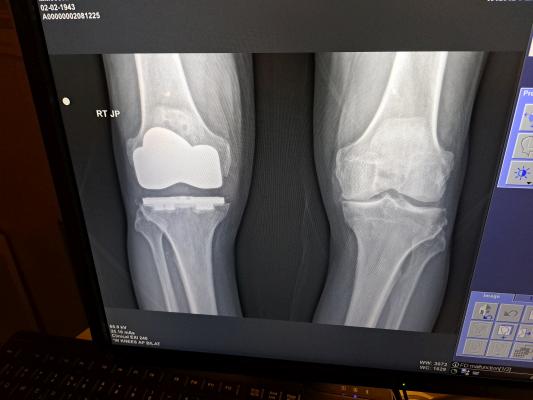

Dad's New Knee - November 4, 2022

. Right Knee -- Left Knee

There Is A Piece Between

The Top And Bottom

However Xray Does Not Show It.

Stryker Knee .